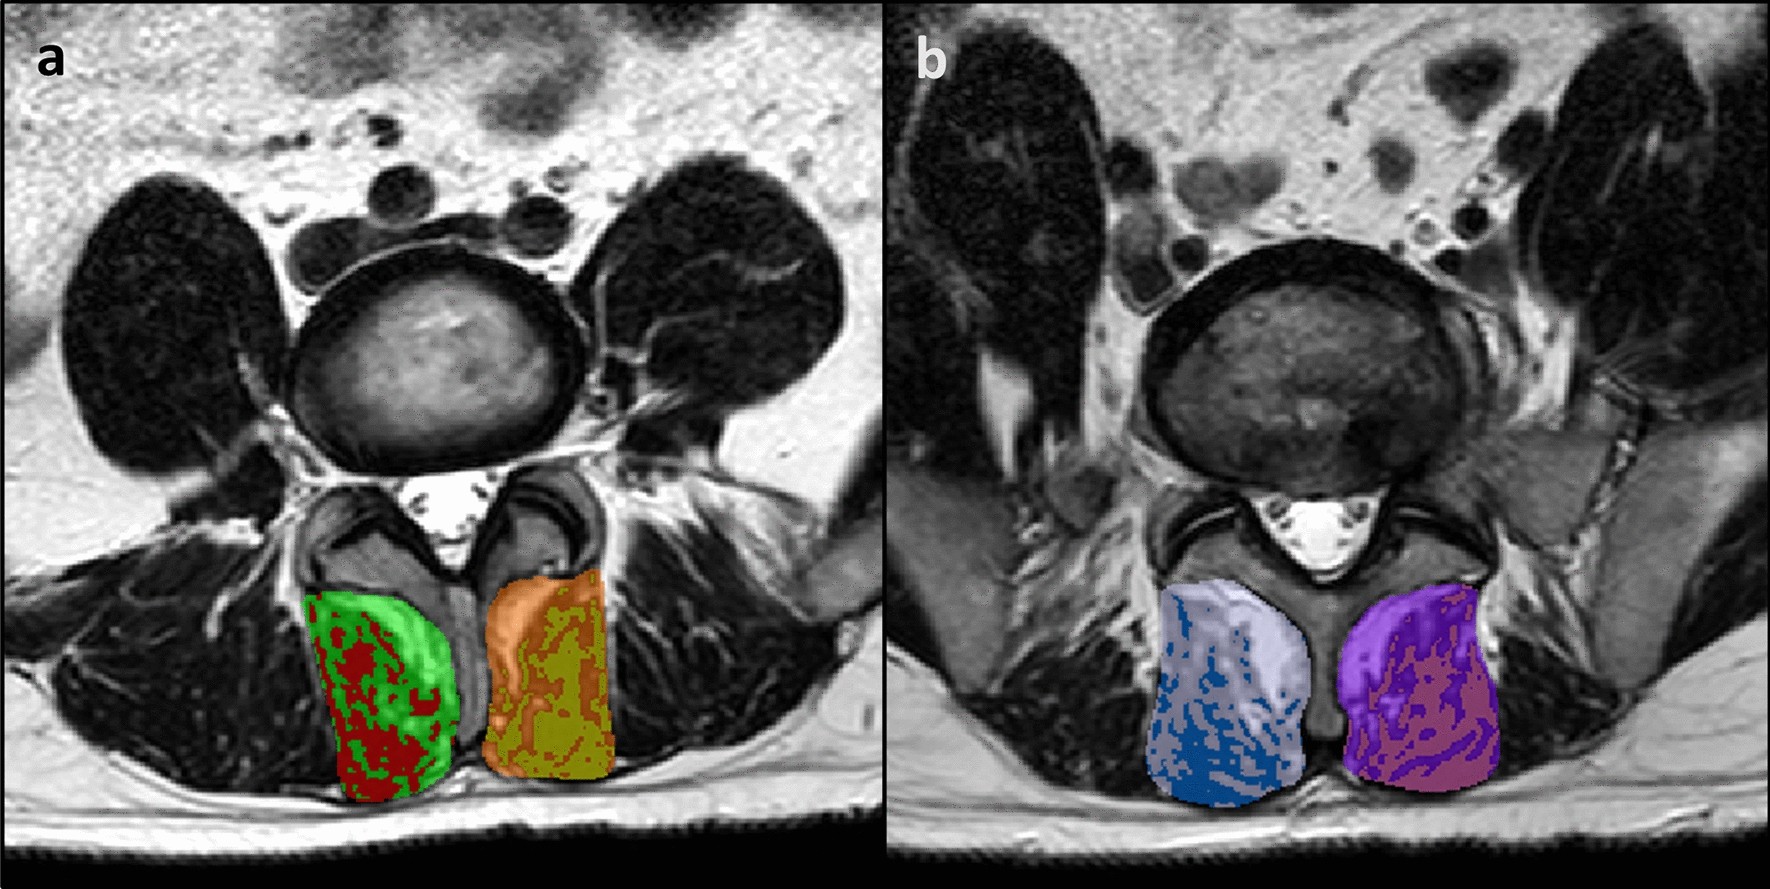

Figure 2

Multifidus muscle total CSA and % MCSA. (a) bilateral total CSA (L4), with red and gold highlights indicating the right and left peak muscle CSA, respectively; (b) bilateral total CSA (L5), with blue and pink highlighting the right and left peak muscle CSA, respectively. Note This method did not select all potential muscle signal; only the “purest” muscle tissue was highlighted.